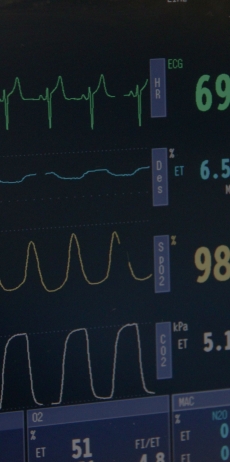

This involves an injection into a vein in your forearm, and you then drift into a deep sleep. While you are unconscious the anaesthetist gives you medications to make your muscles go limp, and controls your breathing with a help of a ventilator (a machine that pushes in oxygenated air into your lungs a certain number of times each minute, through a tube that has been placed in your throat). This may sound complicated, but it is a very safe process, and your bodily functions (especially the workings of your heart and your lungs) are monitored very closely all along - the picture alongside shows a monitor screen. You wake up at the end of your operation like waking up from deep sleep.